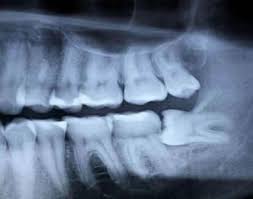

Wisdom Teeth Removal What To Know Before You Get Them Out Delta Dental Of Washington

Is the removal of wisdom teeth covered by health insurance? Cost of wisdom teeth removal can range from $75 to $250 per tooth. The wisdom tooth removal for a full bony impaction can cost you anywhere from $325 to $500. Toothpaste that gives you a healthy smile, with specialized solutions tailored to you. For most people, wisdom teeth usually erupt fully and have a normal positioning.